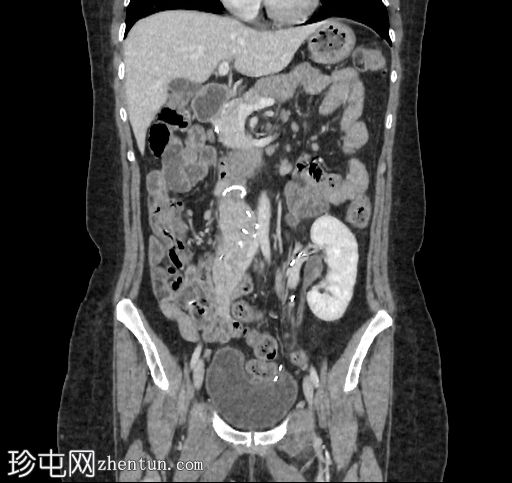

冠状位增强扫描

门静脉期

自体肾脏和胰腺(胰头、胰体和胰尾)明显萎缩。

移植的胰腺位于右侧腹膜后间隙,大小和形态(轴位、冠状位和矢状位)均正常,可见相关手术缝合线。供体十二指肠段与自体十二指肠吻合。可见胰腺移植物与右髂血管的动脉吻合,胰腺实质强化均匀,提示移植物灌注良好。

左髂窝肾移植(轴位、冠状位),显示移植肾与同侧髂总血管的动脉和静脉吻合。移植肾形态完整,实质均匀强化。

本例中,影像学检查显示原位肾脏和胰腺明显萎缩,符合长期糖尿病合并慢性肾脏病的表现。肾移植位于左髂窝,与同侧髂血管的动脉和静脉吻合通畅,肾实质均匀强化,这些影像学表现均符合功能性肾移植的影像学特征。移植胰腺位于右侧腹膜后,形态和位置均符合原位胰腺,供体十二指肠袢与原位十二指肠吻合良好。